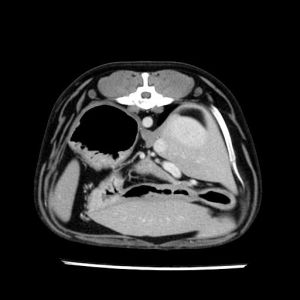

La lesione focale epatica , la ceus,la Tac e il chirurgo .